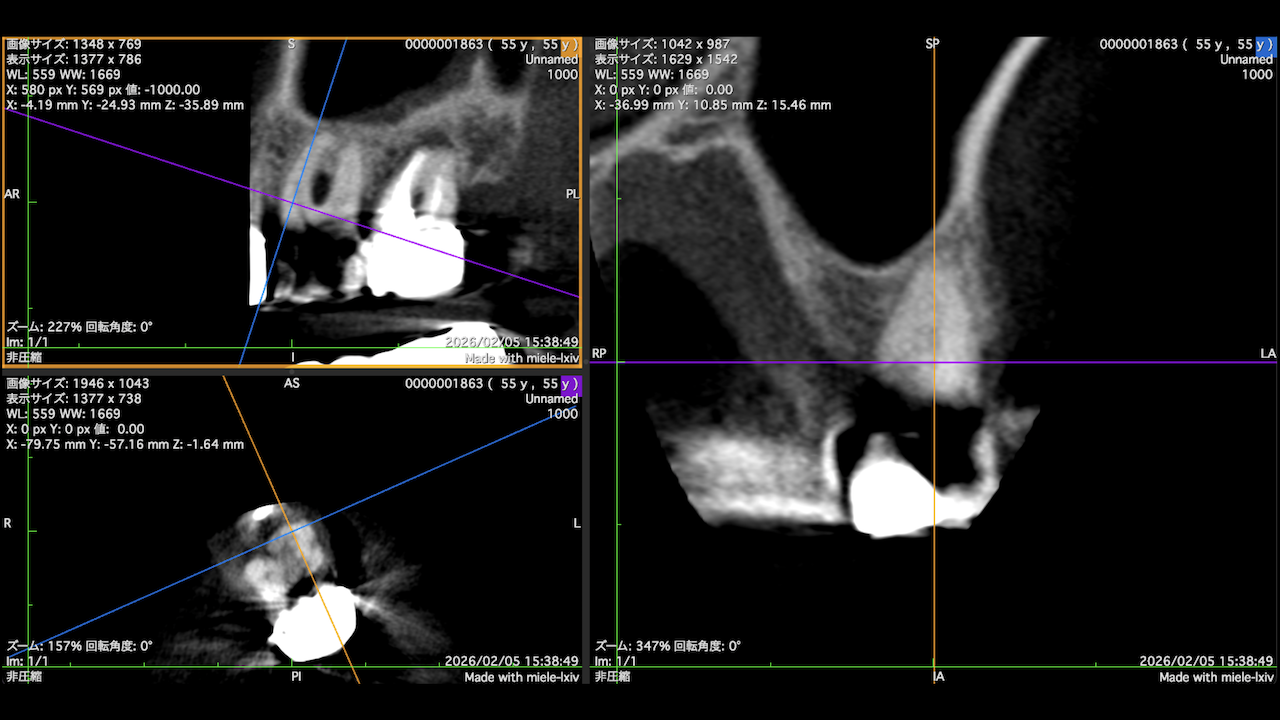

もう1ケースが以下だ。

#7がCold testに無反応である。

故に、#7,8の非外科的根管治療を行うことになった。

が、#8のメタルコアは外しにくいだろう。

CBCTでは2本とも口蓋側の皮質骨が消失している。

という絶望的な状況である。

が、

術前にその予後を患者さんに説明し、

治療へ移行した。

その結果、

ここから4ヶ月が経過すると…

臨床症状も皮質骨も大きく治癒している。

1年後の予後が気になるところであるが、すごくよくマネージメントできているだろう。